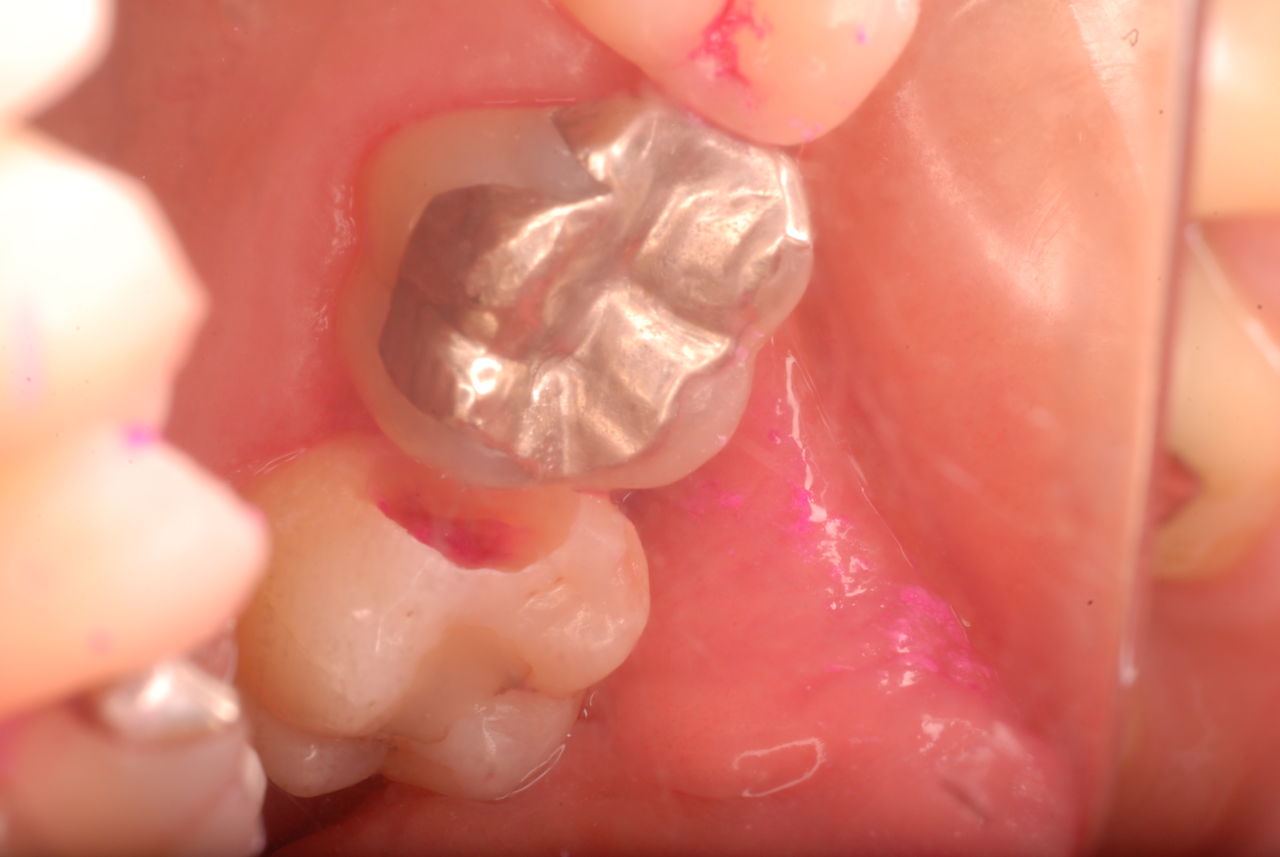

写真は典型的な取り残したまま銀歯を入れていた方のものです。よくぞ痛くならなかったものです。

意外と手間取り一時間以上かかりセメントを入れてとりあえず終了いたしました。神経が近いので傷つけて損傷すると助かる見込みが少なくなり、痛みが出て死んでしまうとか膿んでしまうこともあるのです。![570b1c06-s[1]](https://livedoor.blogimg.jp/netdental/imgs/6/0/60221eb2.jpg)

写真は殆ど崩壊し抜けたセラミックとその後修復してまだ経過監査中の歯の状態です。奥の歯は、重症の歯周病で注射もせずに抜いた歯です。